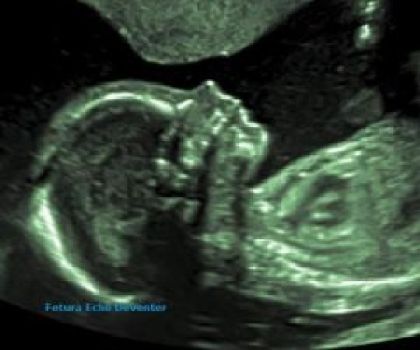

2D echo geslachtsbepaling

Ben je benieuwd naar het geslacht van je baby? Vanaf 14 weken kunnen we meestal goed zien of het een jongetje of een meisje is. Je kunt bij ons een echo laten maken, waarbij we je het geslacht vertellen. Natuurlijk krijg je foto’s en een USB-stick met de beelden mee naar huis.